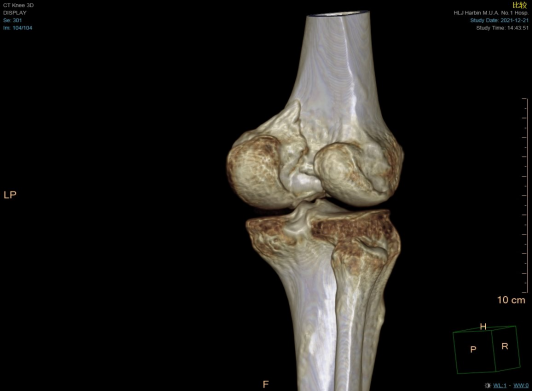

术前三维CT显示股骨内侧后髁冠状位骨折

为减少患者的身体和经济负担,谷文光根据三维CT等影像学资料,把关节镜技术和创伤骨科技术有机结合,制定了关节镜直视下微创复位,经皮通道螺钉固定修复半月板的手术方案。